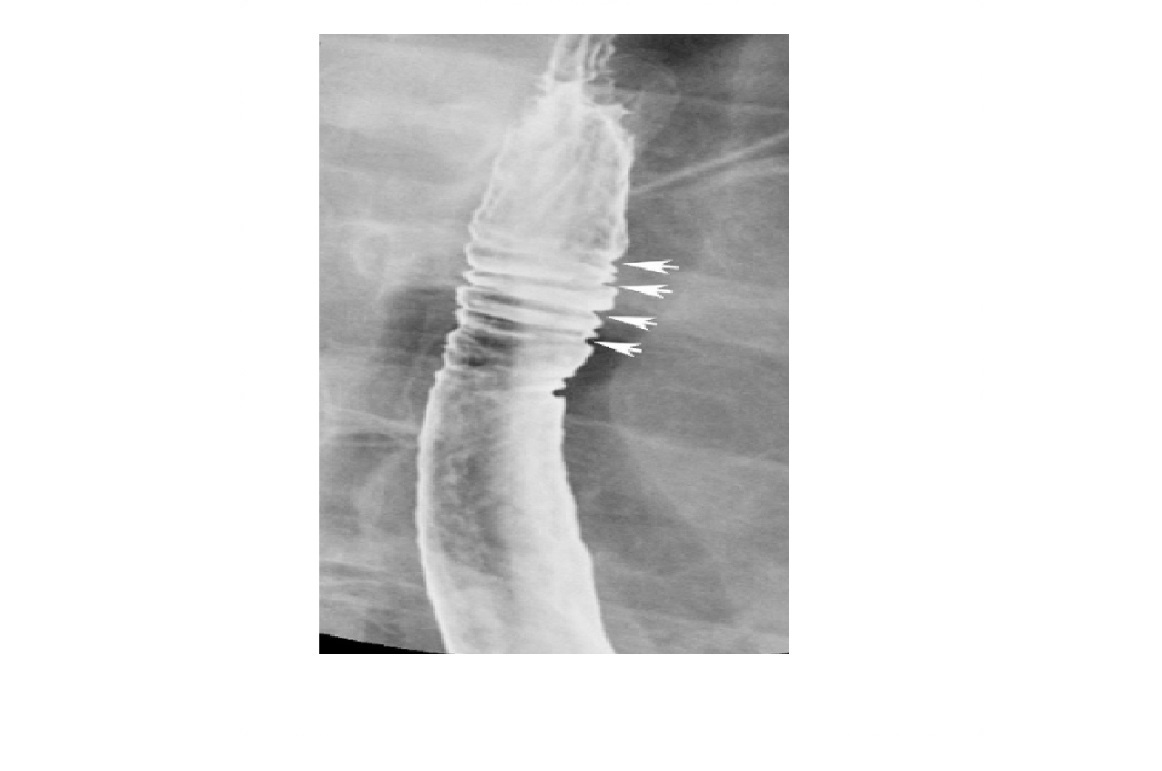

Eosinophilic oesophagitis

Barium - Concentric, ring-like strictures of oesophagus

**Not transient - Permanent **

DDx

feline oesophagus

- folds1-2 mm thick and run horizontally around the entire circumference of the esophageal lumen.

- The findings are transient, seen following reflux and not during swallowing.

- Associated with GORD

- distal two-thirds of the thoracic esophagus